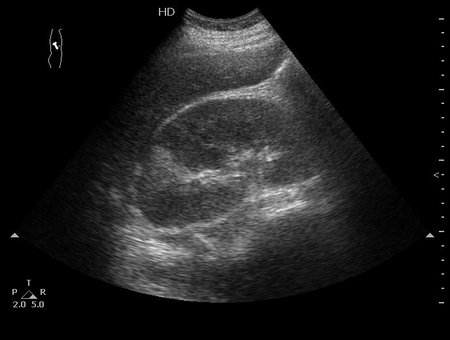

Роженица, во время беременности случилась почечная колика, стентирована.

Боли справа, повышение температуры.

Размеры правой почки 160х80х80мм

Как выглядят собственно апостемы я показать не смогу, так как у меня нет такого замечательного высокочастотного датчика как у вас в детской больнице (вспоминаю сонограммы почек при поликистозной болезни новорожденных здесь на форуме). А вот как выглядит почка с таким заболеванием - см пост 1.

Это - большая почка со сравнительно маленьким центральным эхокомплексом, неравномерно гипоэхогенной паренхимой и отсутствием кортикомедуллярного контраста.